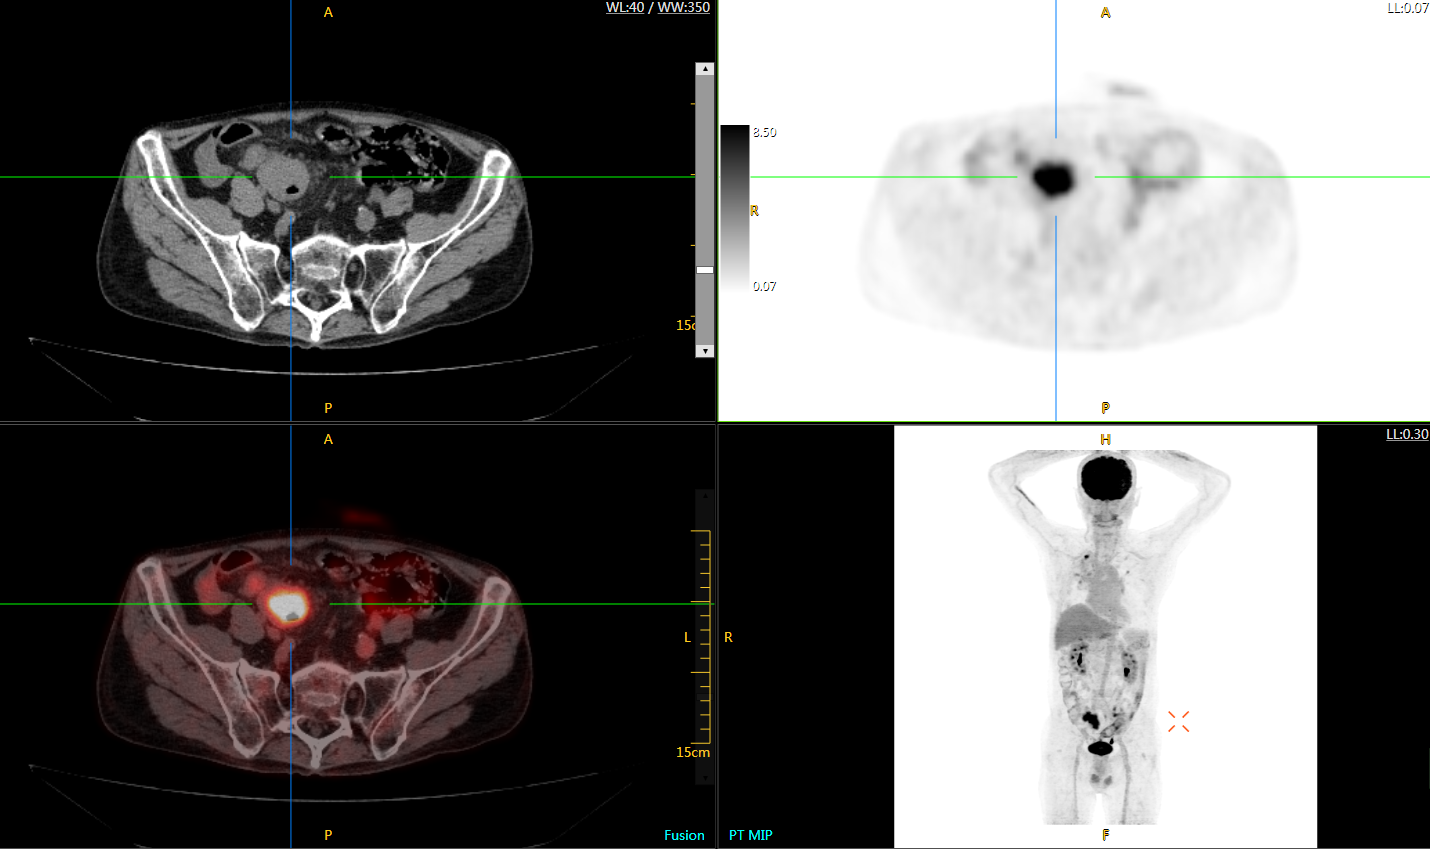

圖例

uExplorer探索者不再局限于傳統(tǒng)靜態(tài)代謝過(guò)程3D成像,而是在此基礎(chǔ)上新增一個(gè)維度——時(shí)間,從而實(shí)現(xiàn)4D全景成像。

注射總劑量為7.8mCi,14分鐘全身采集時(shí)間,在擁有超高靈敏度與超高分辨率的uEXPLORER上,即可得到展示顯示人體諸多精細(xì)結(jié)構(gòu)的高清三維圖像。

注射總劑量為7.8mCi,注射后1.6小時(shí),基于uEXPLORER探索者掃描1分鐘的圖像

注射總劑量為0.67 mCi FDG(低于常規(guī)劑量的十分之一),基于uEXPLORER探索者掃描15分鐘的圖像

注射總劑量為6.9mCi,注射后10小時(shí),基于uEXPLORER探索者掃描14分鐘的圖像